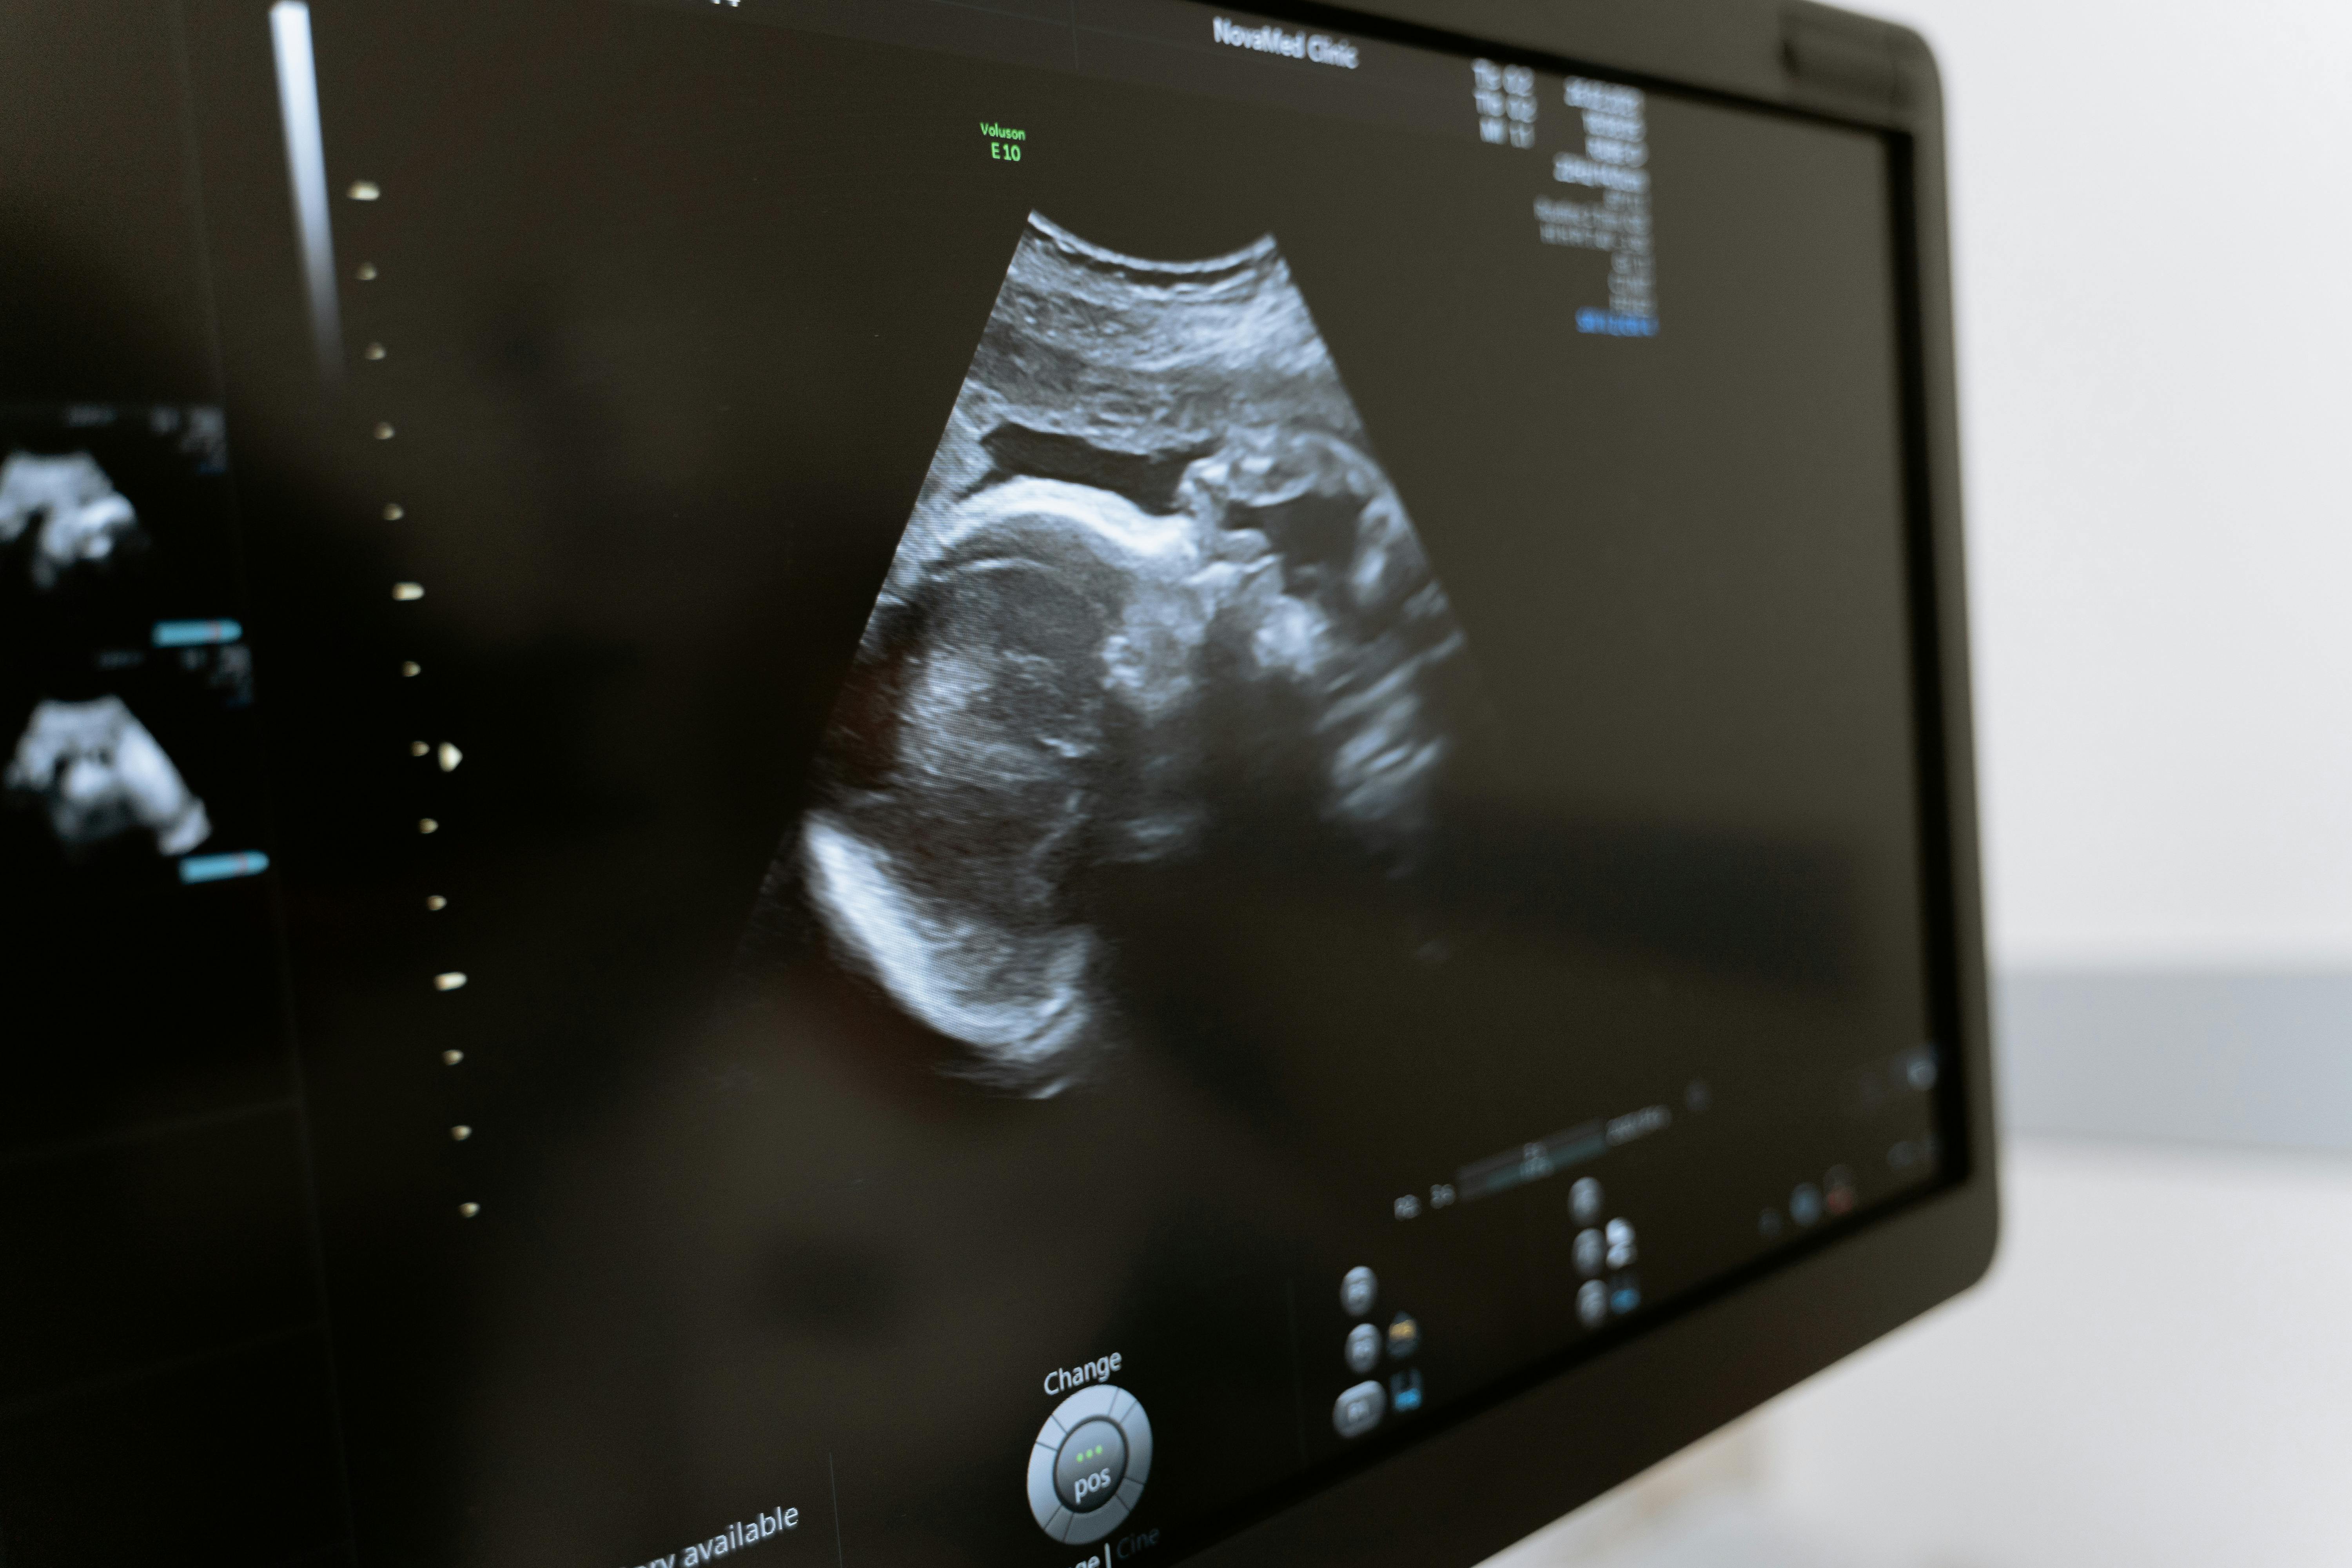

• Ultrasounds: Using sound waves to create images of the pelvic organs and monitor pregnancy.